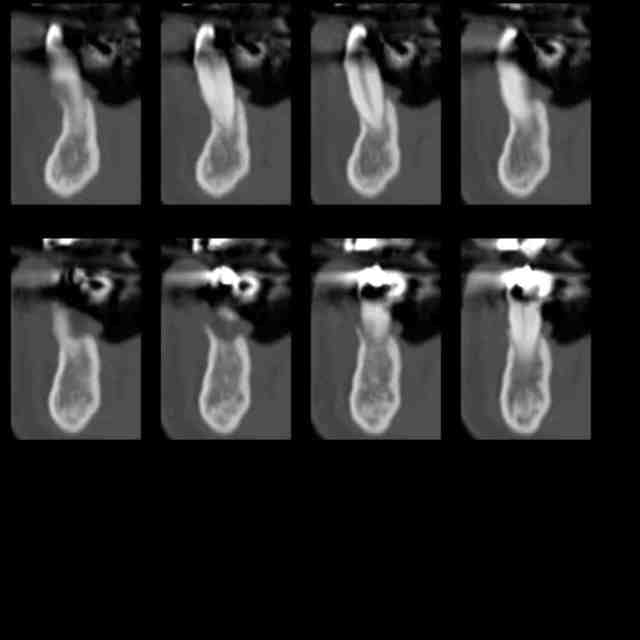

Voilà la pano et les coupes de scan de la dent 44 à 35.

Les suivantes:

Scan 4 azy6ld - Eugenol

Scan 5 go7h1x - Eugenol

Scan 6 kcnfpc - Eugenol